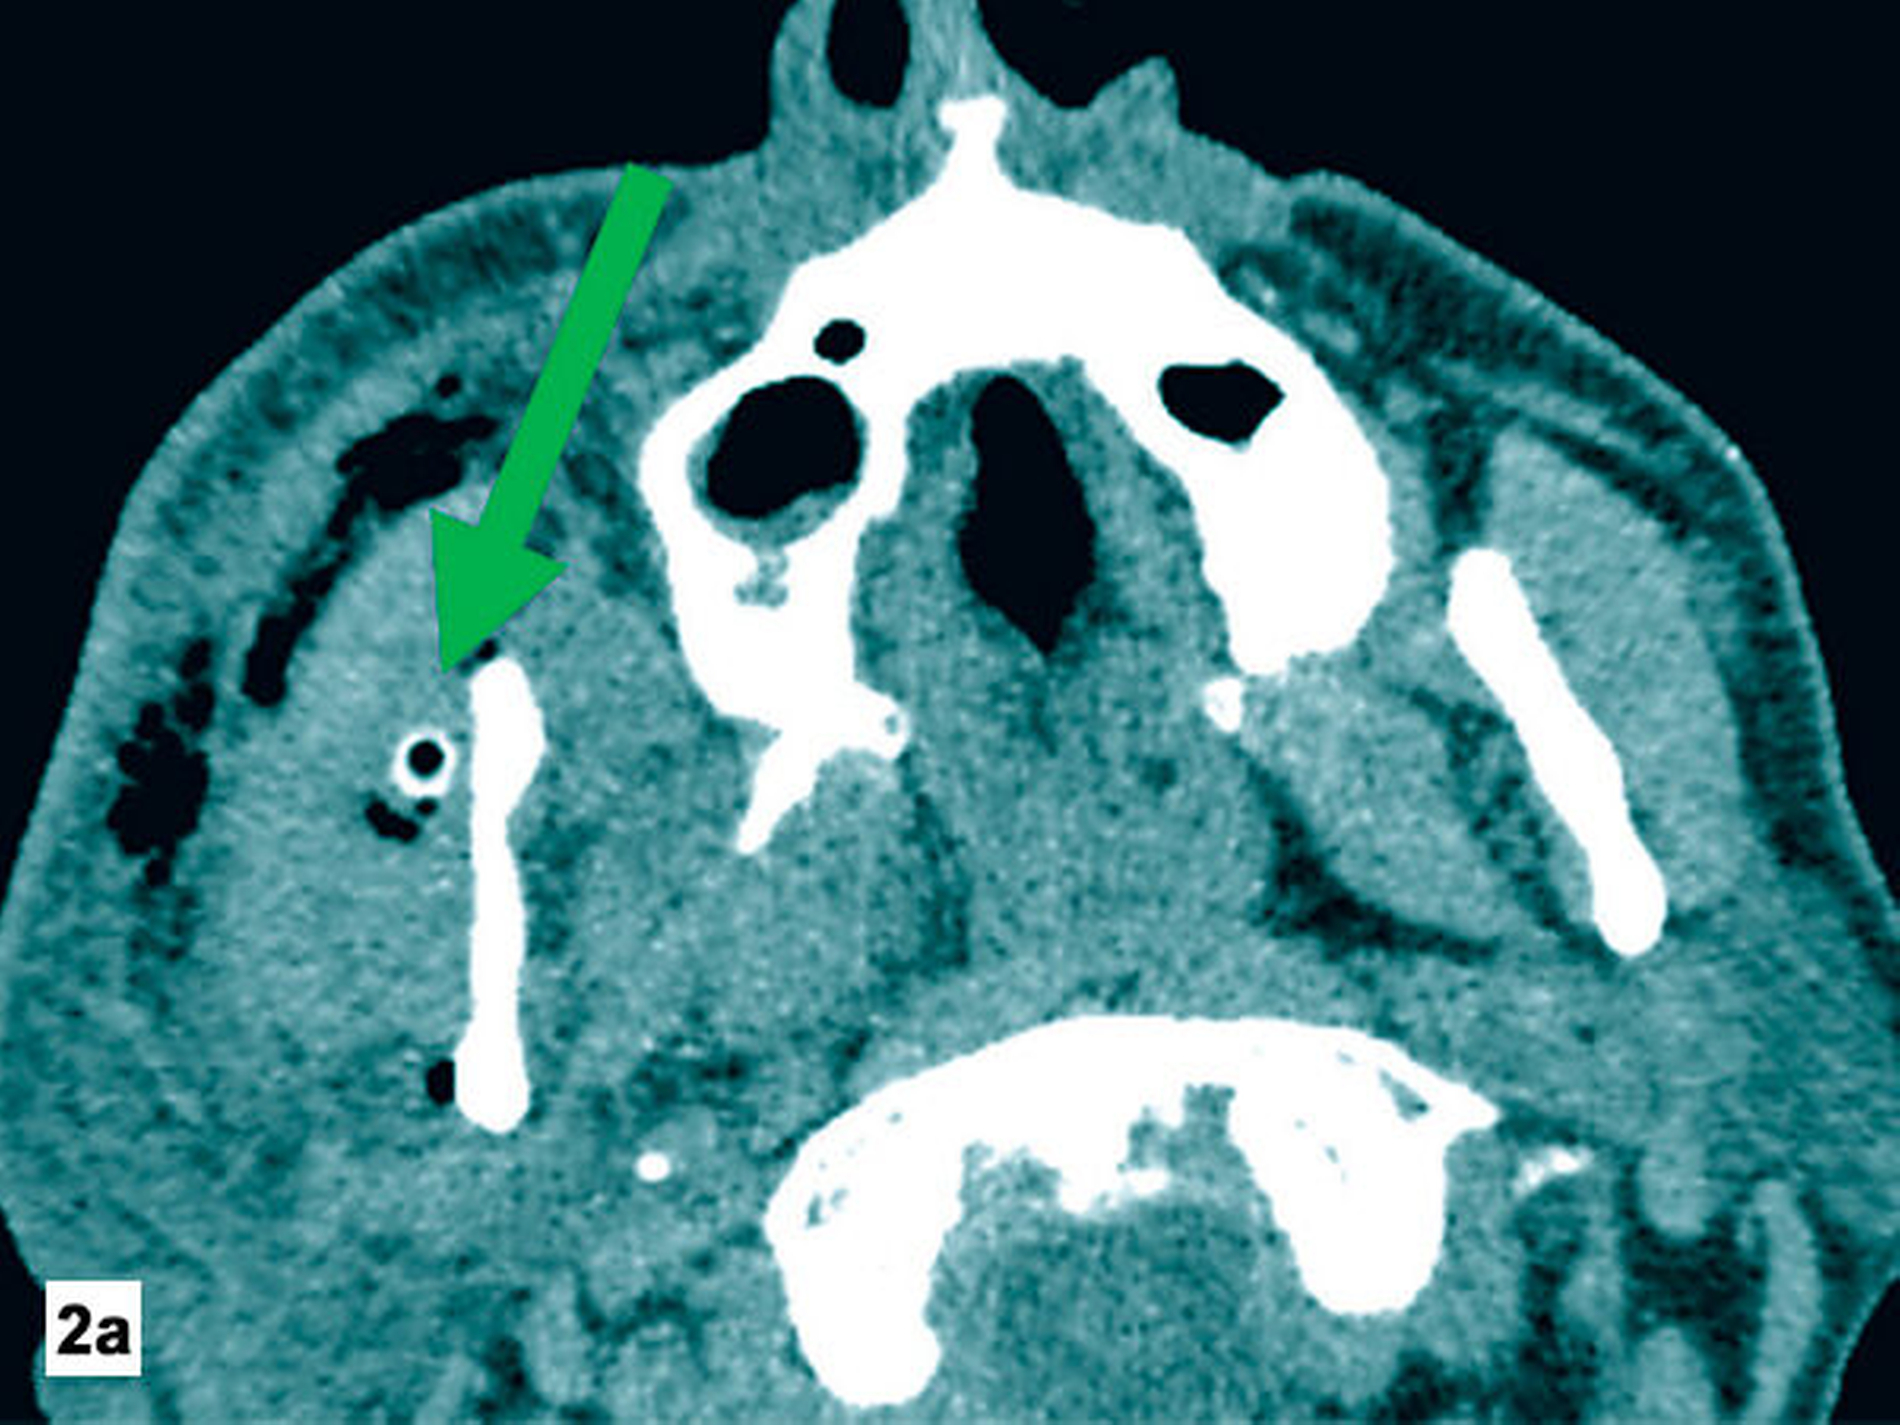

Am Folgetag zeigte der Patient eine zunehmende Verschlechterung und eine progrediente Schwellung der Halsregion mit beginnender Luftnot. Zur erweiterten Diagnostik wurde eine Computertomografie (CT) der Kopf-Hals-Region durchgeführt (Abbildung 2). Hier zeigten sich ein Flüssigkeitsverhalt submandibulär rechts trotz loco typico einliegender Drainage sowie Gewebseinschmelzungen und Gasblasen entlang des rechtsseitig-zervikalen und temporalen Faszienverlaufs.

Zur Diagnostik wird eine Schnittbilddiagnostik, in der Regel eine Computertomografie, empfohlen. Hierbei zeigen sich, wie im hier vorliegenden Fall, typischerweise Luftansammlungen und Gewebseinschmelzungen. Die Abgrenzung von Kutis und Subkutis ist regelhaft nicht mehr möglich [Kämmerer et al., 2017]. Das Vorliegen einer nekrotisierenden Fasziitis kann zusätzlich mit dem „Laboratory Risk Indicator for Necrotizing Fasciitis Score“ (LRINF) eingeschätzt werden, der positiv-prädiktive Wert wird in fortgeschrittenen Stadien mit 92 Prozent angegeben [Wong et al., 2004].